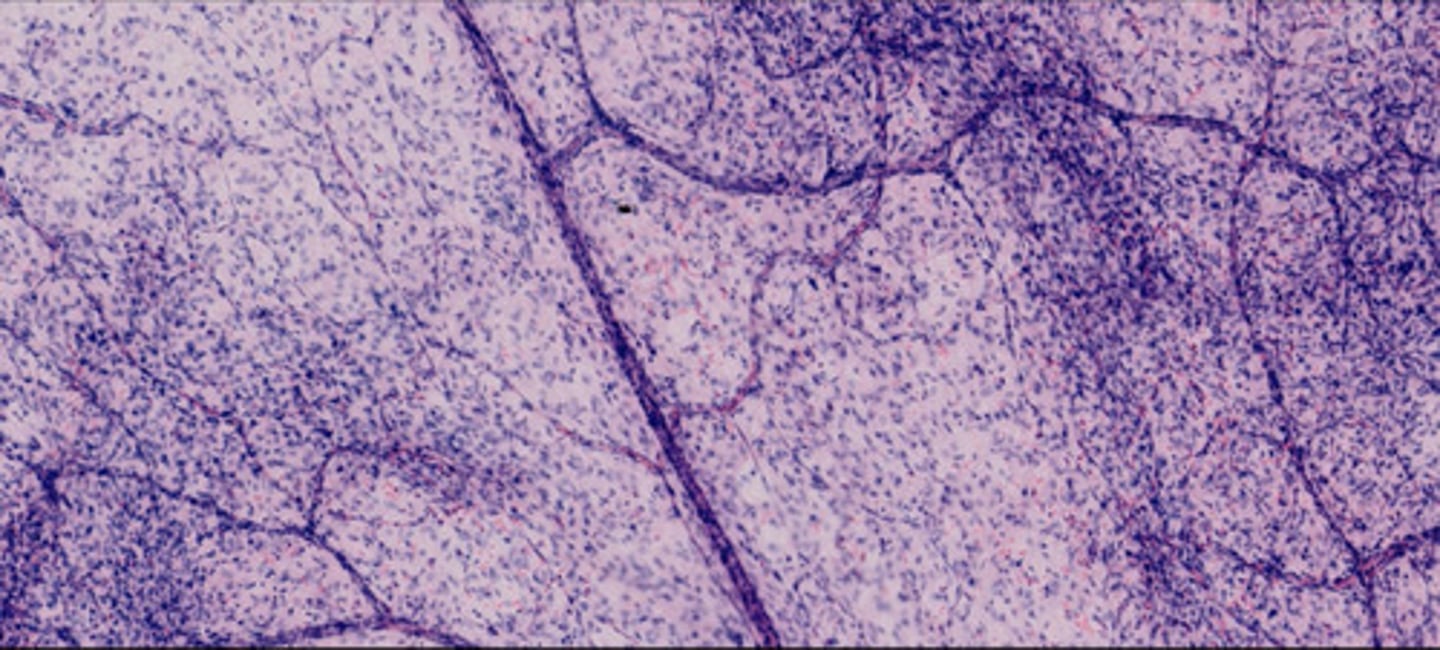

Węzeł chłonny (H+E)